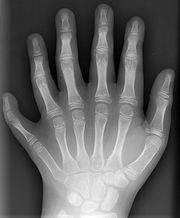

Polydaktylie

Rentgenový snímek levé ruky desetiletého chlapce se šestiprstostí

Polydaktylie je vrozená vada jež má za následek větší počet prstů na noze či ruce než je běžné. Často bývá tato vada dědičná.